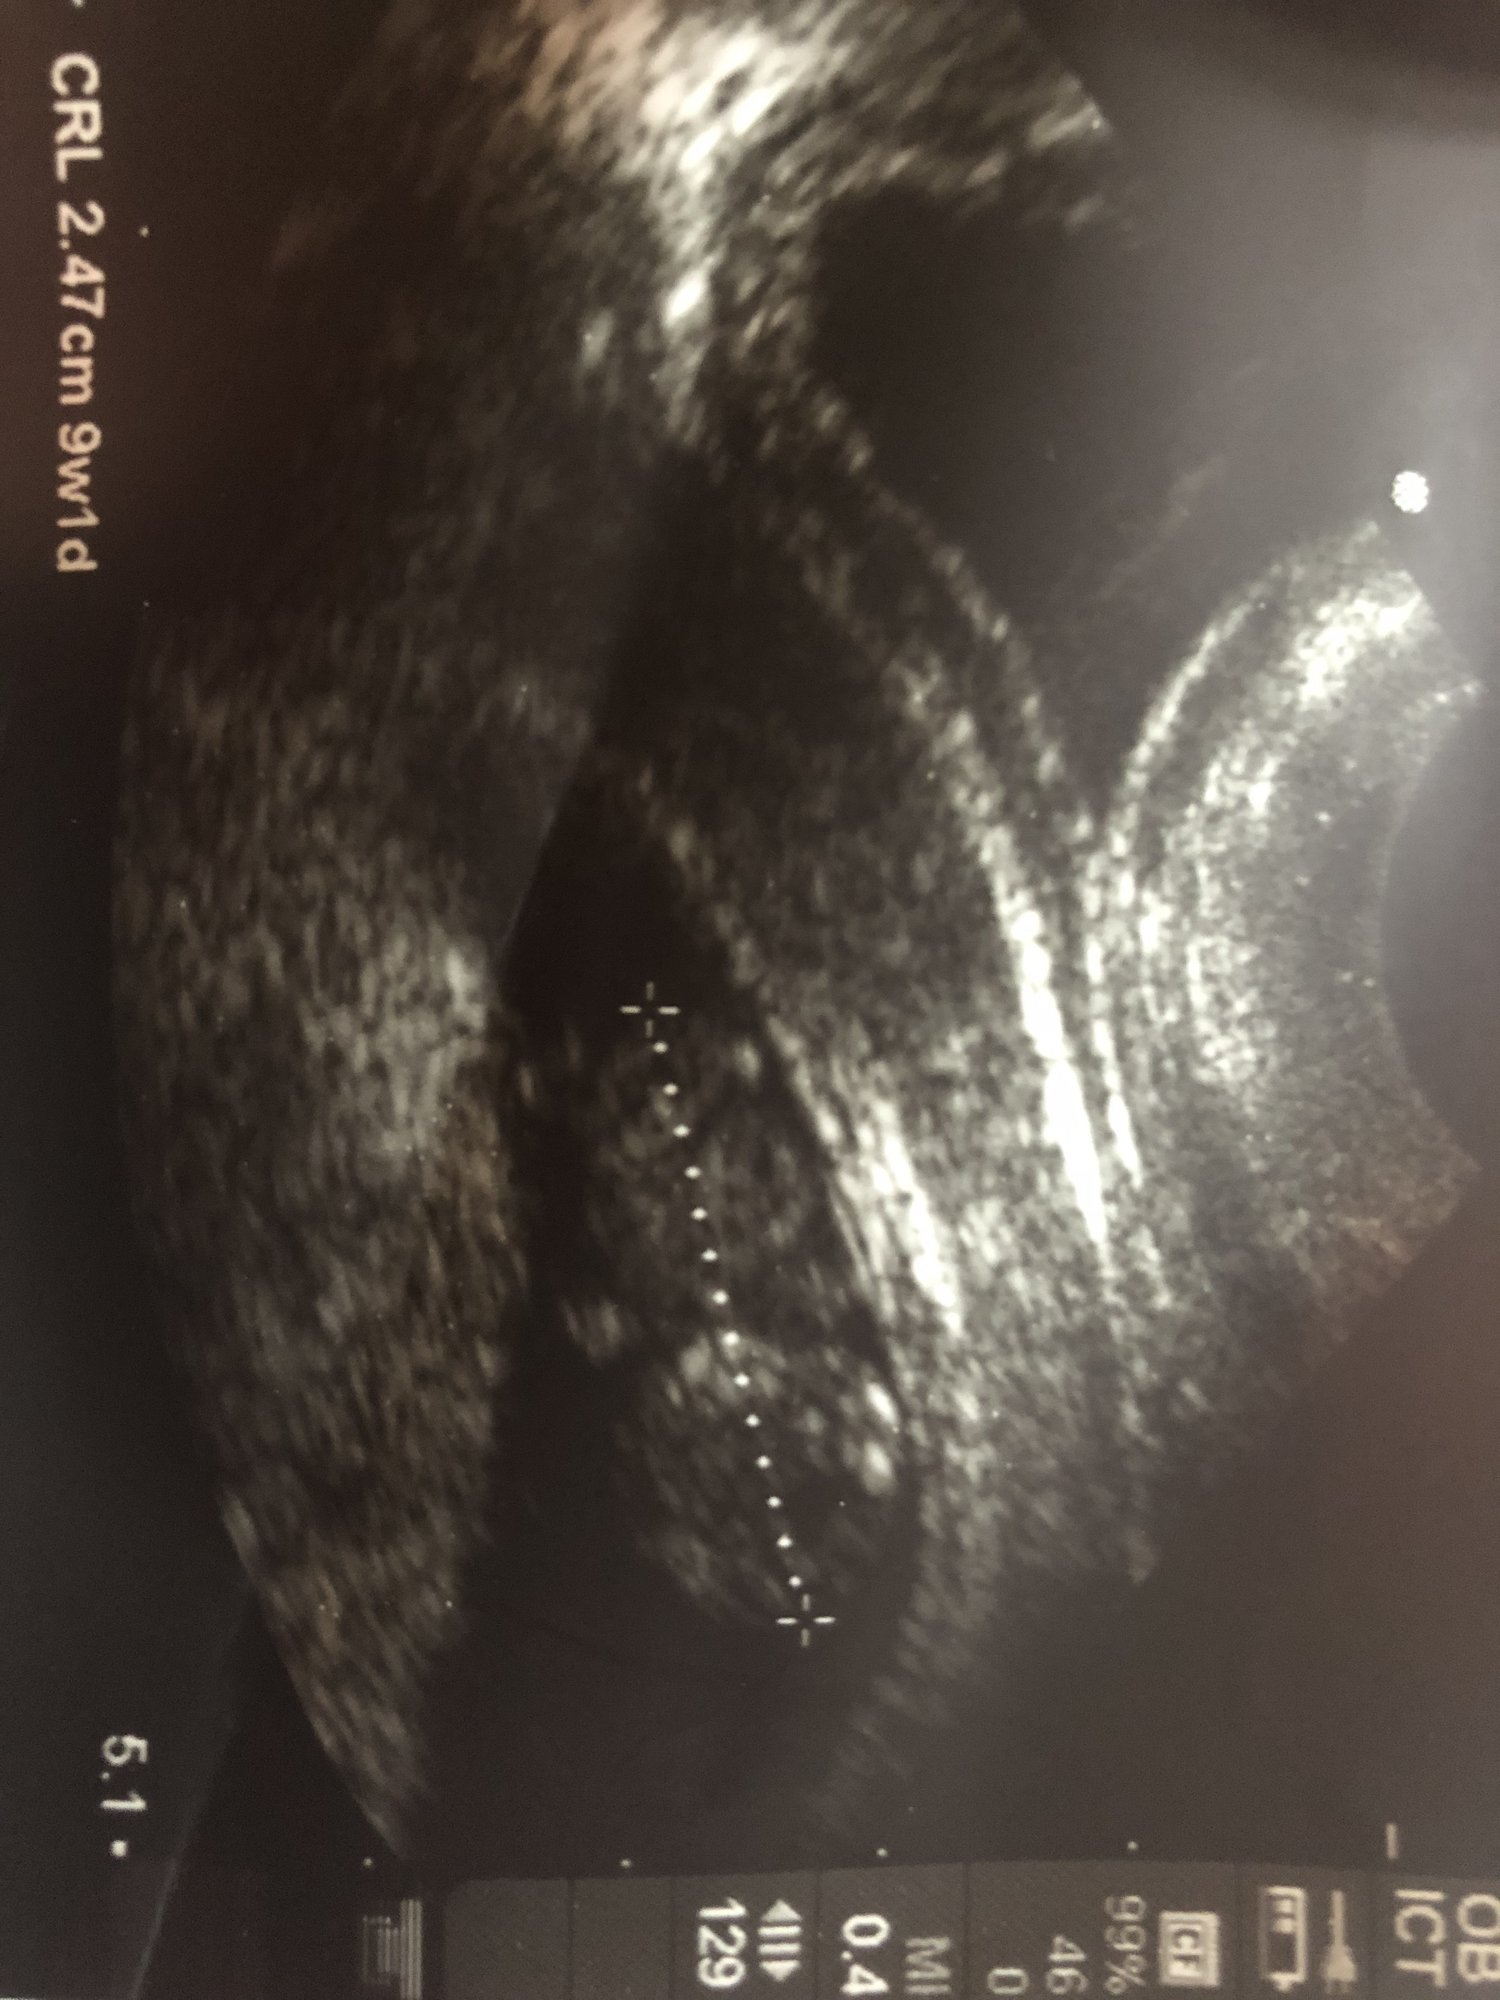

• I had my first ultrasound on Monday! I'm not as far along as I thought - I thought I was past 10 weeks but I'll be just 10 weeks tomorrow. So glad I decided to have an early ultrasound - last pregnancy I just had one at 20 weeks. This time around I was having cramping and bleeding and something seemed off. I guess this is why!!!! Seeing double!! They think identical but can't quite be certain yet as I only wanted an abdominal ultrasound this visit. Needless to say I'm freaking out! New due date of November 8th instead of the 3rd...but I'm sure with twins it may be October!